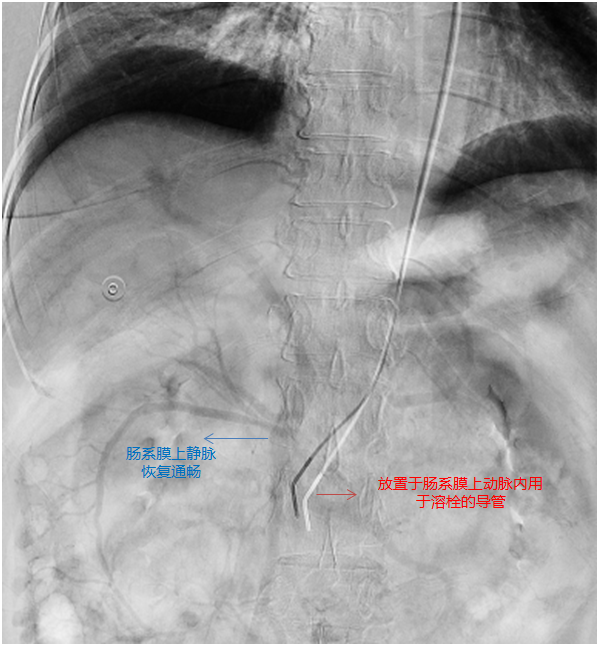

▲ 经过溶栓后肠系膜上静脉恢复通畅

手术由王兵教授及崔文军主任医师指导,安乾、任菲副主任医生进行操作。通过造影定位,精确地将溶栓导管置于肠系膜上动脉内,顺利完成手术。经过术后三天的溶栓,杨奶奶所有的不适症状迅速缓解。再次造影显示,肠系膜上静脉血栓已经被溶解殆尽,血液回流恢复通畅,化验指标也趋于正常,疾病得到良好的治疗。经过施敏护士长团队的精心护理,平稳的度过了围手术期,目前已顺利康复出院。